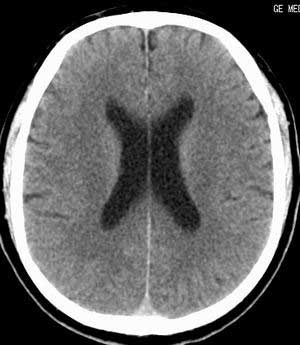

患者男,58岁。耳爆震伤后耳聋2年余,而后双耳道肿胀,间断性流脓。近一月来头痛、恶心、呕吐,右眼红痛,不能入眠。

脑实质密度均匀,未见异常密度灶,脑沟裂池室形态大小正常,中线结构居中.

有条件来个mri扫描吧!!!

建议mr检查可轴、冠、矢多体位,mr 可以发现ct不能发现的许多异常影像。

建议行mr检查排除右枕硬膜下脓肿可能。